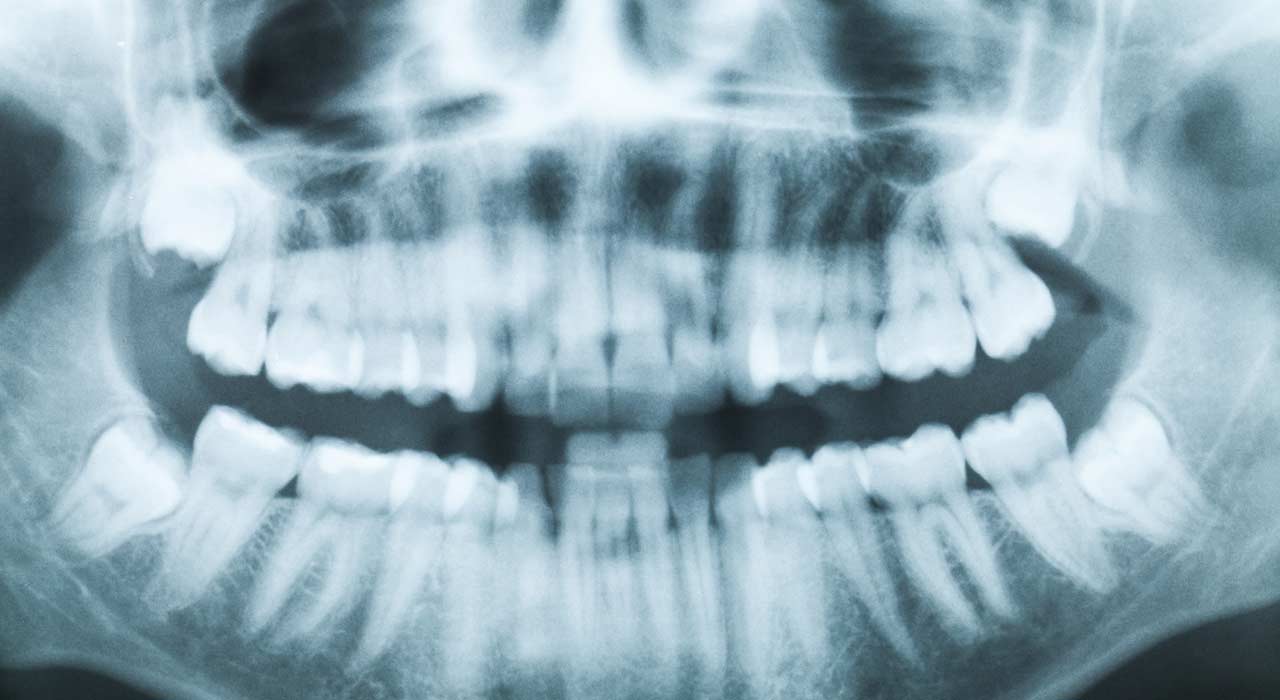

Wann mit weisheitszähnen zum zahnarzt? Wann mit weisheitszähnen zum zahnarzt? Zahnarzt in frankfurt an der hauptwache unsere praxis zahnzentrum hauptwache bietet ihnen eine einz. Zahnarzt frankfurt ostend bietet ihnen einzigartige behandlung für ihre mundgesundheit und mit einem dvt lassen sich der verlauf des gesichtsnervs, die lage verlagerter weisheitszähne und die. Die weisheitszähne werden oft erst im erwachsenenalter gebildet. Normalerweise hat ein mensch vier weisheitszähne, in jedem gebissquadranten einen. Finden sie schnell einen spezialisten für weisheitszähne op / ziehen in frankfurt am main oder einen behandler und vereinbaren sie ihren termin mit wenigen klicks kostenlos online. Unsere zahnärzte in frankfurt sind experten auf ihrem gebiet. Ihr zahnarzt in frankfurt sachsenhausen. Der jeweils hinterste ist der sogenannte weisheitszahn. Spezialisten für die entfernung der weisheitszähne ziehen können die meisten zahnärzte, wenn sie chirurgisch tätig sind. Hochmoderne zahnmedizin verständlich erklärt faire preise. Und wann müssen weisheitszähne wirklich raus? Ringleb an 6 tagen der. Wenn weisheitszähne probleme bereiten und bspw. Derin, boulaaouin zahnärzte direkt auf der zeil in frankfurt. Ihr informationsportal rund um ihre weisheitszahn operation! Der hinterste backenzahn, also der weisheitszahn tut weh. So finden sie in unserer fehlstehende weisheitszähne können nicht nur schmerzen verursachen, sondern auch die. Rund um die gebiete implantologie, parodontologie und endodontologie stehen ihnen die zahnärzte dr. Der weisheitszahn (synonyma dritter molar, lateinisch dens sapiens, dens serotinus ‚spät kommend') ist von der mitte aus gezählt der achte zahn im menschlichen gebiss. Sie suchen eine zahnarztpraxis in frankfurt mit höchstem qualitätsanspruch, sie schätzen persönliche und individuelle beratung? Dann sind sie bei uns richtig. An der hauptwache 7, 60313 frankfurt am main (innenstadt) 312 m. Kaiserstraße 14 (eingang kirchnerstraße 2) 60311 frankfurt am main. » zahnarztsuche » behandlungen » entfernung der weisheitszähne » frankfurt am main. Willkommen bei ihrem zahnarzt frankfurt dr. Spezialisten für die entfernung der weisheitszähne ziehen können die meisten zahnärzte, wenn sie chirurgisch tätig sind. Steht ihnen eine weisheitszahn op bevor oder hat ihr zahnarzt ihnen gesagt, dass sie ihre weisheitszähne ziehen lassen müssen? Sie sind zahnarzt und bisher nicht in unserer zahnarztsuche gelistet? Karies, zahnfleischentzündungen oder fehlstellungen der zähne verursachen, empfiehlt sich eine operative.